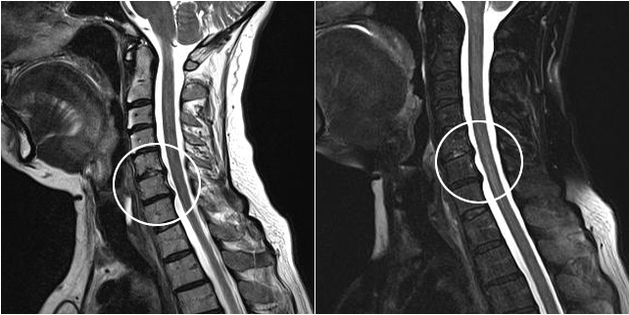

Modern diagnostic methods include MRI and CT, which make it possible to more accurately examine the processes of destruction of cartilage and bone tissue.Also, using this technique is suitable for diagnosing hernias and other soft tissue defects near the source of the disease.